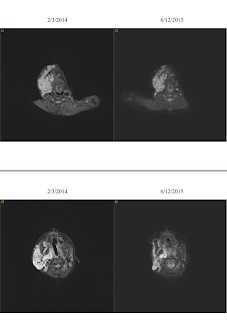

I’m going to show one more set of

pictures—it’s a bit confusing at first if you are not used to looking at MRIs, but

what follows is a side-by-side images of the same slice of Jane’s tumor from

2/2014 compared with now. Tumor is the

big white blob on the left of the image.

You can see in some spots where it appears to have just melted! (You can also see from these images why her

tumor can’t be surgically removed—it wraps around everything.)